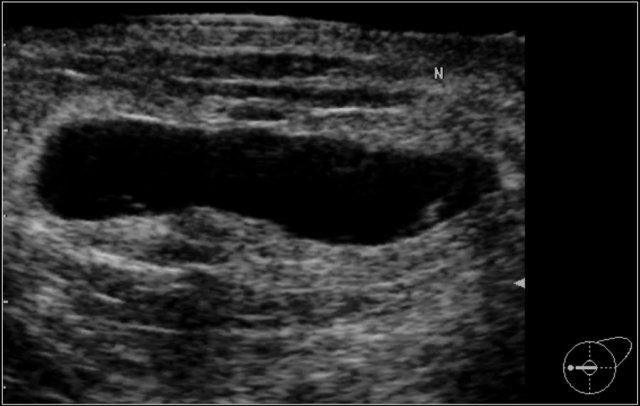

Bệnh nhân này được phát hiện có một khối trên phim nhũ ảnh tầm soát, được phân loại là BI-RADS 0 (cần đánh giá hình ảnh bổ sung).

Siêu âm bổ sung cho thấy khối này là do một hạch bạch huyết trong tuyến vú gây ra.

Đánh giá cuối cùng là BI-RADS 2 (tổn thương lành tính).

Đừng quên đề cập trong báo cáo rằng hạch bạch huyết trên siêu âm tương ứng với khối không vôi hóa trên nhũ ảnh.

Trong phần về vị trí, chúng ta sẽ thảo luận về cách xác định chắc chắn rằng hạch bạch huyết tìm thấy trên siêu âm chính là khối đã thấy trên nhũ ảnh.